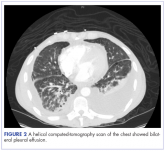

ArticleBilateral chylothorax in an AIDS patient with newly diagnosed Kaposi sarcomaAuthor:Rebecca Neril et alPublish date: June 29, 2017Read More